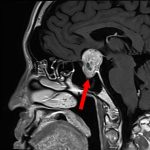

手術前1

手術前2